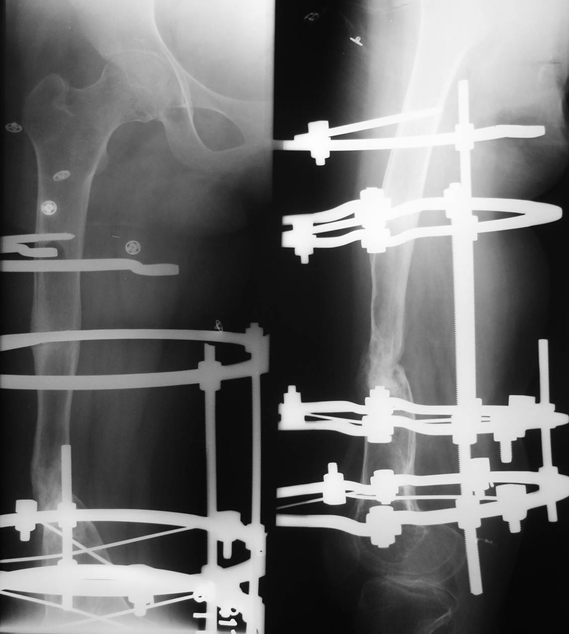

Figure 1: Radiographs at presentation showing infected non-union of femur

Figure 2: Radiographs after debridement, primary docking and Ilizarov ring fixator application

Figure 3: Radiographs showing union at fracture site with Ilizarov fixator in situ

Figure 4: Radiograph at the time of last follow-up, showing fracture union

Of the total of 30 patients, union was achieved in all patients. The mean time to union was 7.41 ± 1.01 months (range, 6 9 months). A case study is shown in Figures 1 to 4. Two patients developed wound infection which required repeated debridement and dressings along with prolonged broad spectrum antibiotic cover. Four patients had pin tract infections which were managed by local dressings and oral antibiotics. Five of them developed pin loosening during the course of treatment. Despite established infection at the beginning of the treatment, the rate of complications by the Ilizarov method was significantly low with p < 0.01. Average deformity at the fracture non-union site at the end of treatment was 6.40Ί ± 4.05Ί (range, 0Ί - 15Ί). Mean shortening at the time of final follow-up was 3.36 ± 0.99 cm (range, 0 to 5 cm). Sixteen patients had more than 3 cm limb length discrepancy (p = 0.7153). This was accepted as a price to pay for achieving union at the non-union site by compression.